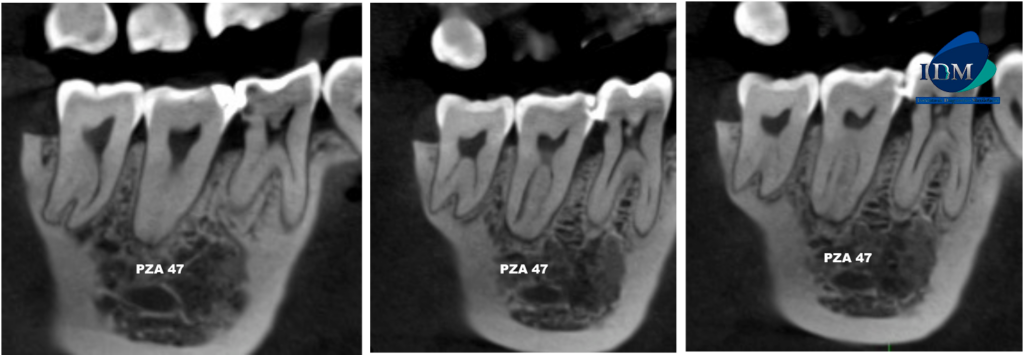

CORTES AXIALES

A la evaluación de la tomografía volumétrica (cone beam) en los cortes axiales (Figura 2), tangenciales (Figura 3) y en la reconstrucción 3D (Figura 4) se observa en la pieza 47 la configuración del conducto radicular en forma de “C” desde tercio cervical hasta apical.

Fan et al. (2004) proponen una clasificación de los conductos radiculares en forma de “C” (1) . Esta clasificación es anatómica y se representa en los cortes axiales de tomografía volumétrica (TCHC).

- Categoría 1 (C1), la raíz tiene una sección transversal continua en forma de C sin separación ni división.

- Categoría 2 (C2), la raíz tiene una sección transversal discontinua en forma de C con al menos un arco no inferior a 60°.

- Categoría 3 (C3), la raíz tiene 2-3 canales separados y ningún arco es mayor de 60°.

- Categoría 4 (C4), la raíz tiene un solo conducto redondo u ovalado en la sección transversal.

- Categoría 5 (C5), el conducto radicular no tiene lumen, pero el conducto suele estar cerca del ápice.